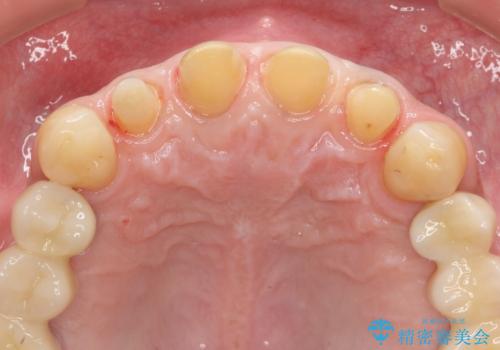

虫歯のマイクロスコープによる丁寧な除去、根管治療、深い虫歯に対する挺出(エクストリュージョン)および歯周外科を行ったのち精度の高いセラミッククラウン製作治療を計画します。

虫歯の放置により、根管治療や深い虫歯に対する処置が必要になりましたが丁寧に一つづつ処置を行ったことで抜歯をすることなく歯を残すことができました。

セラミッククラウンの製作をする前に、歯内・歯周環境の整備は非常に大切です。